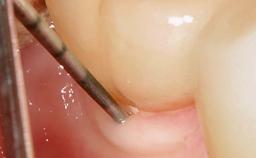

Resective Surgical Treatment of Peri-Implantitis Including Implantoplasty

In this case, Myroslav Solonko, Ignacio Sanz Sánchez and Mariano Sanz present a treatment that aims to eliminate exposed implant threads by modifying the implant surface, converting a moderately-rough surface into a smooth surface.

A 63-year-old male patient was referred to the post-graduate periodontal clinic of the Complutense University of Madrid for the treatment of peri-implantitis. According to the patient’s record, all his maxillary teeth had been extracted ten years previously due to severe periodontitis, and a full-mouth implant-supported restoration on eight implants was placed. No supportive periodontal therapy was provided apart from occasional check-ups by the restorative dentist.